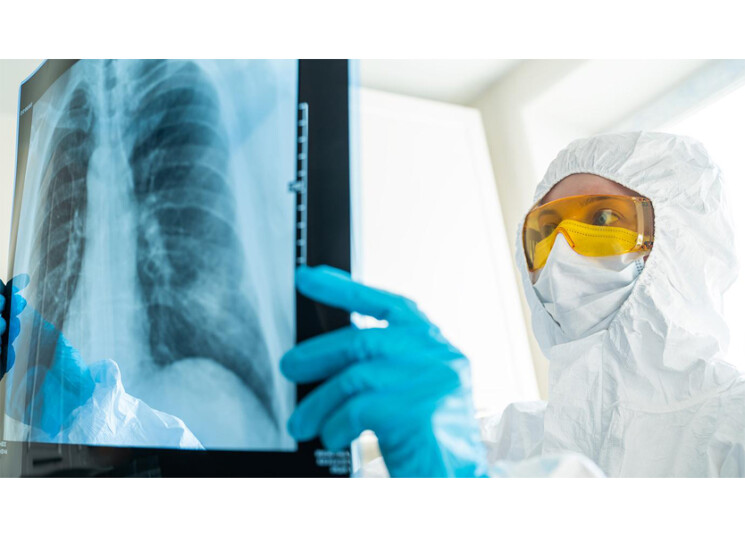

خلصت دراسة جديدة إلى أنّ مرضى كورونا، الذين عولجوا في المستشفيات، يعانون تلفاً في الرئة يستمر لعدة أسابيع بعد عودتهم إلى المنزل، في أعقاب شفائهم من الفيروس المستجد.

وفي التقييم الأول، كان أكثر من نصف المرضى يعانون عارضاً واحداً على الأقل، وهو في الغالب ضيق التنفس والسعال. لكنّ صور الأشعة أظهرت تلفاً في الرئة بنسبة 88 في المئة لدى المشمولين في الدراسة.

وفي التقييم الثاني، تحسنت الأعراض وانخفضَ تلف الرئة إلى 56 في المئة فقط من العيّنة، فيما لا يزال من السابق لأوانه الحصول على نتائج التقييمات في الأسبوع 24.

وقالت سابينا ساهانيك، الطبيبة والأكاديمية في جامعة إنسبروك، إنّ «الخبر السيئ هو أنّ المرضى يظهرون ضعفاً في الرئة حتى بعد أشهر من خروجهم من المستشفى».

أمّا الخبر الجيّد فهو أنّ حالة الرئة تتحسن بمرور الوقت، ما يعني أنّ الرئتين لديهما آلية للإصلاح الذاتي. ولفتت الأكاديمية النمساوية إلى أنه «لحسن الحظ لم يطرأ أي خلل وظيفي في القلب»، بما يعني أنّ الضرر اقتصر على الجهاز التنفسي فقط.